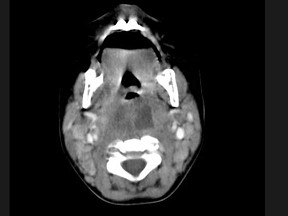

[多选题] 10个月大的婴儿,发热,曾患中耳炎,CT扫描如图所示,请选择正确的描述或诊断()A . 咽后壁软组织肿胀B . 其内密度不均C . 颈椎骨质未见明显异常D . 考虑为咽后壁脓肿E . 考虑为咽后壁寒性脓肿

[多选题] 10个月大的婴儿,发热,曾患中耳炎,CT扫描如图所示,请选择正确的描述或诊断()A .咽后壁软组织肿胀B .其内密度不均C .颈椎骨质未见明显异常D .考虑为咽后壁脓肿E .考虑为咽后壁寒性脓肿